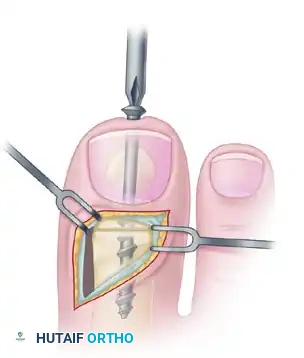

Step 3: Preparation for Interphalangeal Joint Arthrodesis

With the EHL detached, the IP joint is easily accessed.

- Perform a transverse arthrotomy of the IP joint.

- Acutely flex the distal phalanx to expose the articular surfaces of both the head of the proximal phalanx and the base of the distal phalanx.

- Using a microsaw or rongeur, resect the articular cartilage down to bleeding subchondral bone. The cuts should be flat and parallel to permit a neutral position in both the sagittal and coronal planes.

Step 4: IP Joint Fixation (Shives and Johnson Technique)

Rigid internal fixation is paramount for a successful arthrodesis. The use of a 4.0-mm cancellous lag screw, as advocated by Shives and Johnson, provides excellent compression and rotational stability.

- Retrograde Drilling: Drill a 2.0-mm diameter hole longitudinally in a retrograde manner starting at the center of the denuded articular surface of the distal phalanx.

- The drill bit should exit the skin at a point exactly 5 mm plantar to the tip of the nail in the midline of the toe.

- Antegrade Drilling: Appose the denuded articular surfaces of the proximal and distal phalanges in neutral alignment. Insert the drill bit distally at the tip of the toe (through the previously created exit hole) and advance it proximally.

- Follow the previously placed retrograde hole, cross the IP joint, and drill into the base of the proximal phalanx, advancing down the center of its medullary canal.

- Overdrilling and Tapping: To achieve a true lag effect, overdrill the distal phalanx (the near cortex) with a 2.7-mm drill bit to create a gliding hole. Tap the entire drill path with a 3.5-mm tap to prepare for the cancellous screw.

- Screw Insertion: Following the drill path in a proximal direction, insert a 4.0-mm partially threaded cancellous bone screw.

- As the screw head engages the distal phalanx, the lag effect will produce robust compression across the arthrodesis site, ensuring firm fixation.